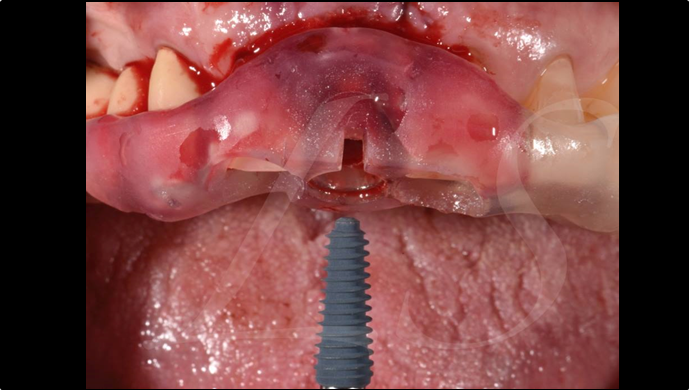

Clinical case: : Immediate loading of lower molars using R2Gate prefabricated 3D-printed provisional restoration

- Courtesy of Dr. Sam Omar, Egypt -

Dr.Sam Omar, immediate loading, digital guided surgery, digital ONE-DAY implant, maxillary anterior, #21, guided surgery, immediate loading, AnyRidge, R2GATE, Mega ISQ, MEG Torq, R2GATE Full Surgical Kit

implant system, R2GATE Guide, R2GATE surgical kit (AnyRidge), Mega ISQ

“ONE-DAY implant, one-day smile

”